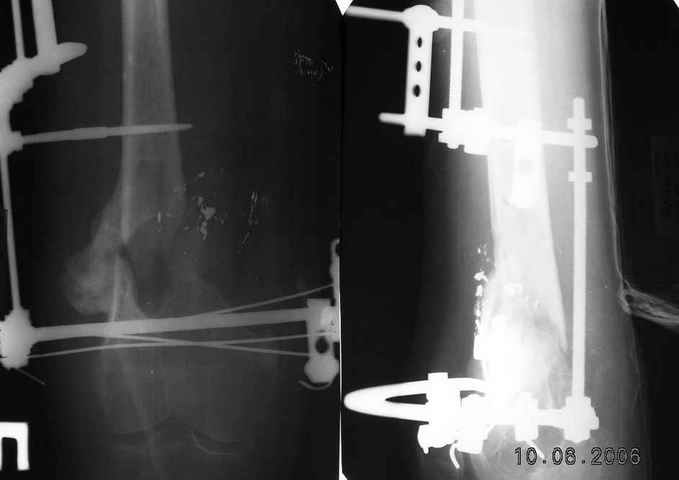

Рефрактур уж точно можно будет не опасаться, а за несколько месяцев даже при отсутствии заполнения костью по всей окружности, этот обходной "мостик" упрочнится и возьмет на себя нагрузку. В приложении пример такого рода "эндопротезирования диафиза", прошло больше 3 лет.

Пациентка, страдающая еще и инсулинозависимым диабетом, не хромает, работает инженером.